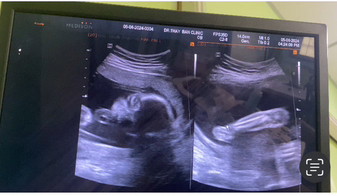

ไม่เน้นโชว์ตัว โชว์แต่ขายาวๆรู้ๆไปเลยว่าพ่อแม่สูงทั้งคู่ 25สัปดาห์